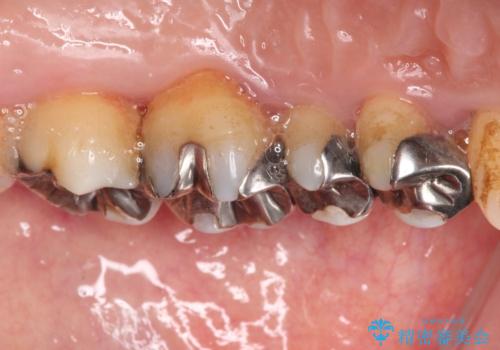

- 奥歯の銀歯をセラミックの白い歯にして、しみる症状も改善したいとのことで来院された患者様です。

知覚過敏の症状が強い歯と、銀歯の範囲や銀歯の下のむし歯が大きい歯は、インレー修復では対応が難しいためオールセラミッククラウンで、インレー修復で対応が可能な歯ではセラミックインレーにて修復することとしました。